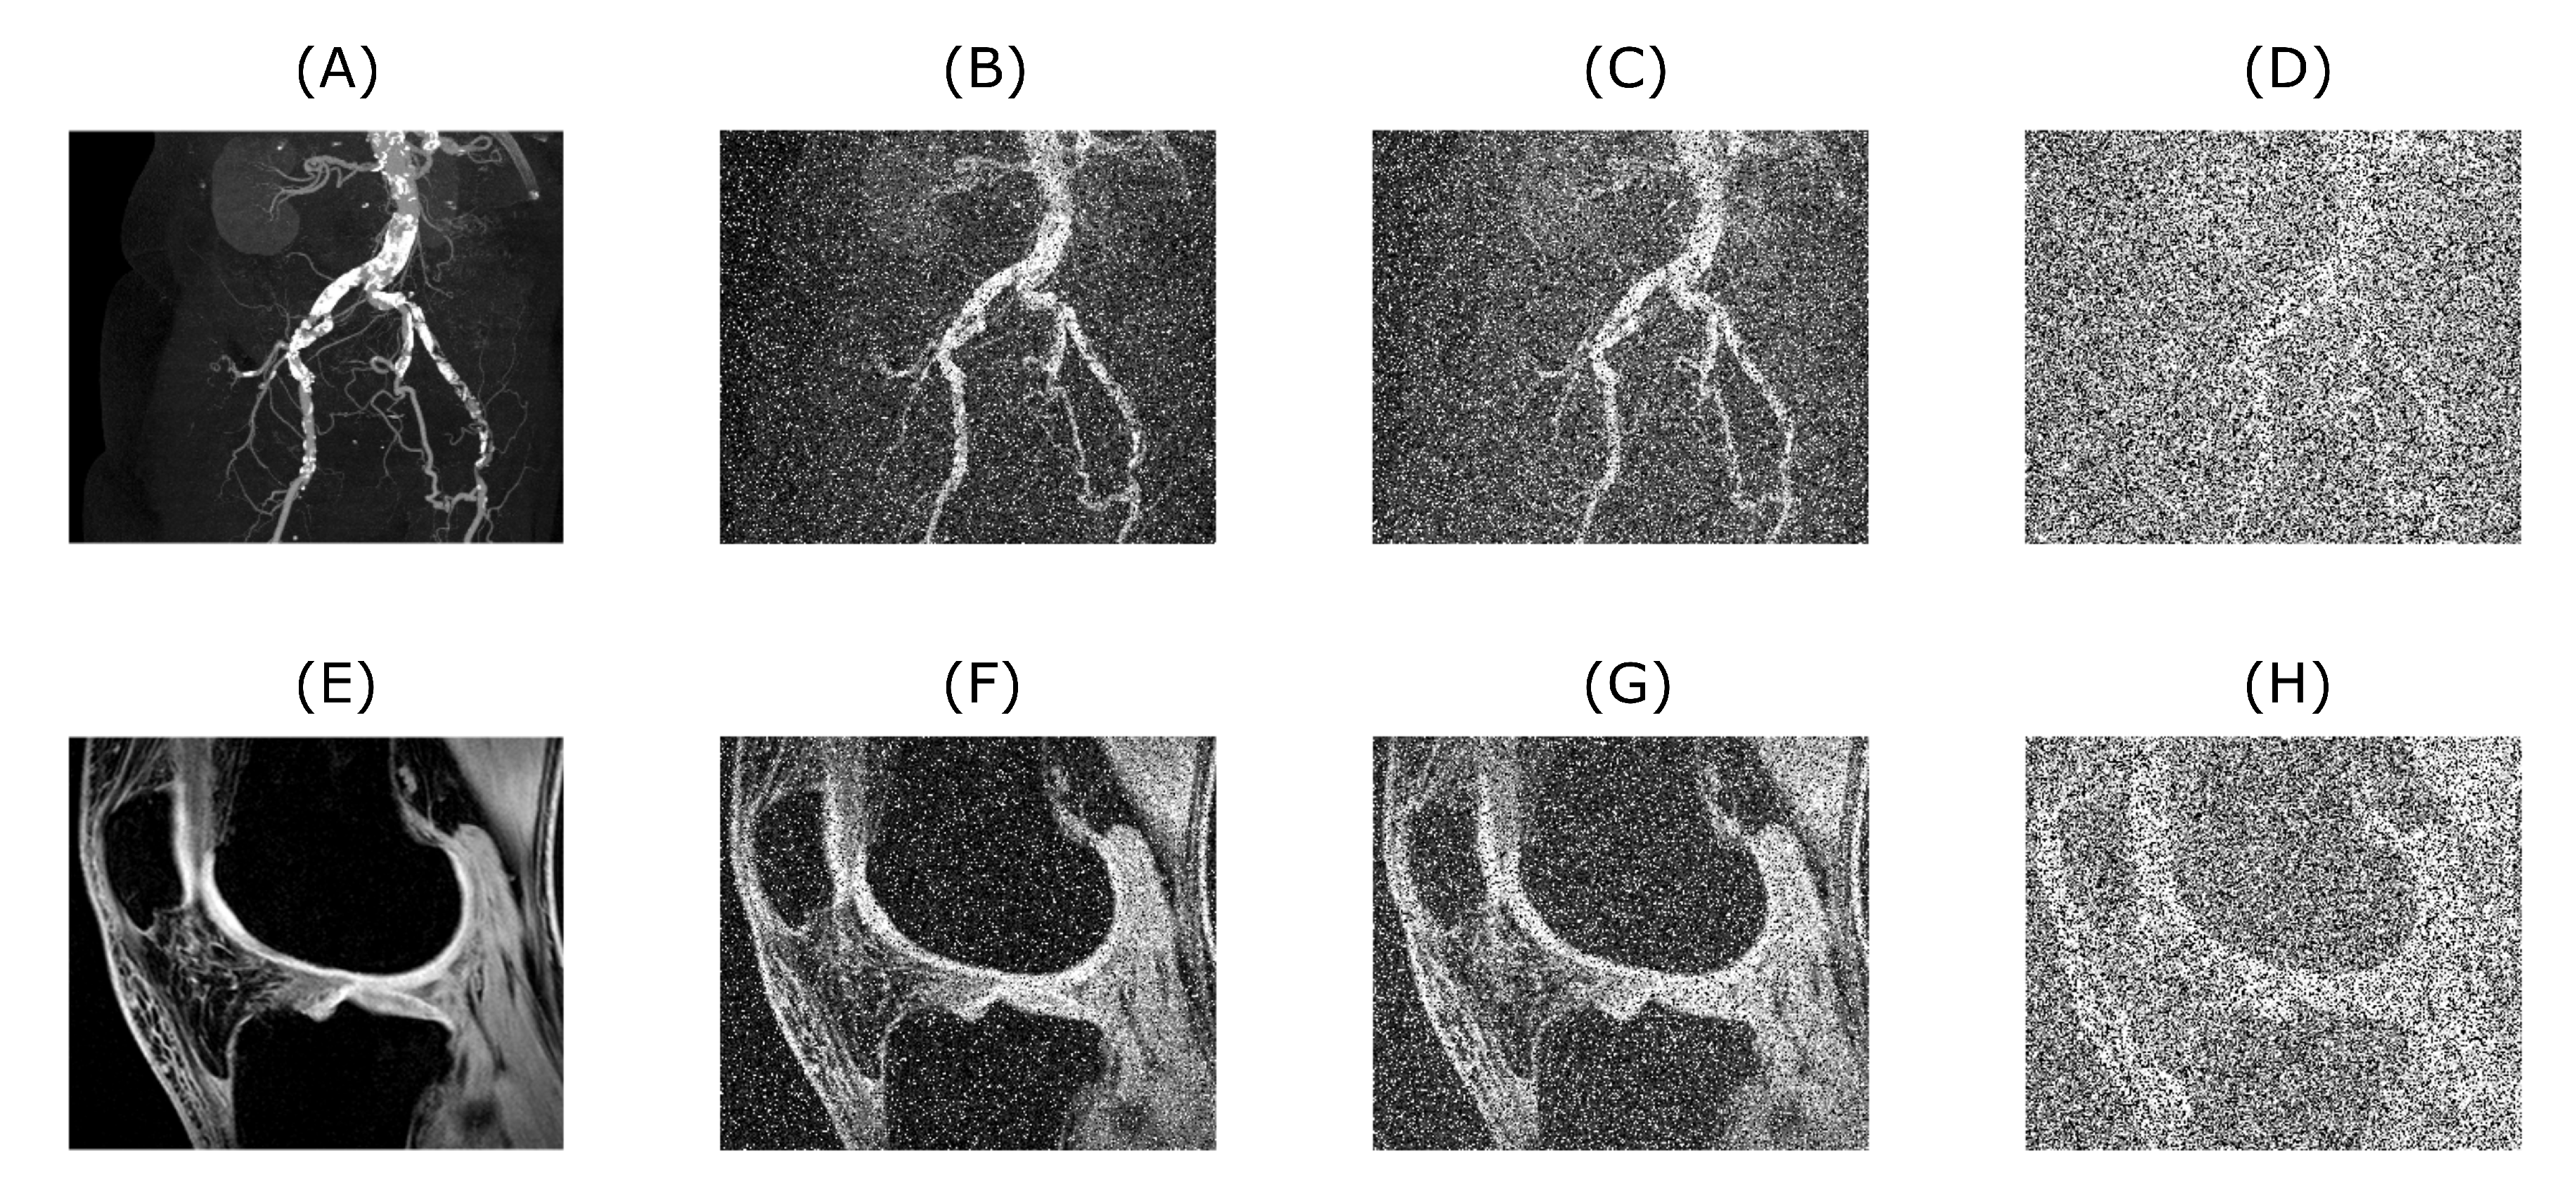

Figure 2.

Upper row is showing a CT scan of blood vessel calcification with the native level of noise (A) used as an input for algorithm testing. Images (B–D) are showing the original image with added artificial noise for 0.1, 0.2 and 0.5 level (in fact the noise consists of a sum of three noise types, in which the number means a mean value for additive white Gaussian noise and density for salt and pepper noise, speckle noise is kept on a constant default value used in MATLAB), respectively. Lower row shows the example of MRI scan of knee cartilage (E used as an input), again with different consecutive noise levels of corresponding magnitude (F–H).